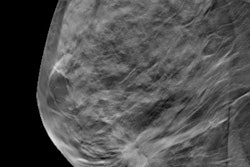

Whether digital breast tomosynthesis (DBT) is more effective than digital mammography for breast screening may depend on the country. An August 4 study in Radiology found that DBT was largely cost-effective at a threshold of $38,500 per life-year gained -- but not at $20,000 per life-year gained.